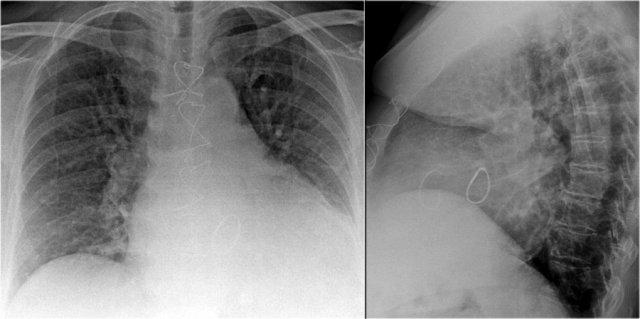

Mạch máu Phổi và Cấu trúc Rốn phổi

Động mạch phổi trái (màu tím) vòng cung phía trên phế quản gốc trái và nằm cao hơn động mạch phổi phải (màu xanh lam), động mạch này đi phía trước phế quản gốc phải.

Hiểu biết về giải phẫu rốn phổi bình thường trên tư thế nghiêng giúp phát hiện các bất thường.

Ví dụ:

- Trên tư thế PA, có thể nhận thấy rốn phổi to, nhưng khó phân biệt giữa giãn mạch máu và hạch to.

- Trên tư thế nghiêng, sự hiện diện của các đám mờ tròn ở những vùng mà mạch máu phổi bình thường không có mặt gợi ý mạnh mẽ đến hạch bạch huyết to.

Trong trường hợp này, bệnh nhân được chẩn đoán sarcoidosis.

Ngoài ra, lưu ý dải cạnh khí quản dày, một dấu hiệu khác của hạch to trung thất.

Một đặc điểm giải phẫu quan trọng cần lưu ý là rốn phổi trái bình thường nằm cao hơn rốn phổi phải.

Mối tương quan này xuất phát từ đường đi của các động mạch phổi: động mạch phổi trái vòng cung qua phía trên phế quản gốc trái, trong khi động mạch phổi phải đi phía trước phế quản gốc phải — vốn thường nằm thấp hơn phế quản gốc trái.

Trong một số ít trường hợp, hai rốn phổi có thể nằm cùng mức, nhưng rốn phổi phải tuyệt đối không được nằm cao hơn rốn phổi trái.

Trong hình minh họa này, các động mạch phổi thùy dưới được tô màu xanh lam để biểu thị máu chưa được oxy hóa.

Các động mạch này có hướng đi thẳng đứng hơn so với các tĩnh mạch phổi, vốn chạy theo hướng nằm ngang hơn về phía nhĩ trái — nằm ở phía dưới so với mức các động mạch phổi chính.

Trên phim X-quang ngực tư thế nghiêng, cả động mạch và tĩnh mạch phổi đều có thể nhận diện được và không nên nhầm lẫn với hình ảnh hạch bạch huyết to. Đôi khi, các tĩnh mạch phổi có thể trông nổi bật hơn bình thường.

Động mạch phổi chính trái đi phía trên phế quản gốc trái và nằm cao hơn động mạch phổi phải — vốn đi phía trước phế quản gốc phải.

Các hình ảnh đính kèm là tái tạo CT lát cắt dày theo mặt phẳng sagittal của lồng ngực, giúp tăng cường khả năng hiển thị các cấu trúc rốn phổi.

Các động mạch phổi thùy dưới đi xuống từ rốn phổi theo hướng thẳng đứng.

Trên phim X-quang, các mạch máu này được gọi thông tục là “ngón út” do kích thước và hình dạng của chúng tương tự như ngón tay út (1).

Trên phim X-quang ngực tư thế thẳng (PA), “ngón út” của động mạch phổi thùy dưới phải có thể quan sát thấy ở khoảng 94% người bình thường, trong khi ở bên trái tỷ lệ này là khoảng 62% (1).